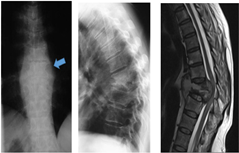

Typical X-ray features of sTB with paraspinal abscess shadow on the AP X-ray (left) and vertebral body collapse on the lateral X-ray (middle) and MRI (right).

Typical X-ray features of sTB with paraspinal abscess shadow on the AP X-ray (left) and vertebral body collapse on the lateral X-ray (middle) and MRI (right). Note the two body involvement, as evidenced by visualising the pedicles and posterior elements. The MRI confirms the anterior column destruction, pus anteriorly and epidurally compressing the compressing the spinal cord in a myelopathic patient.